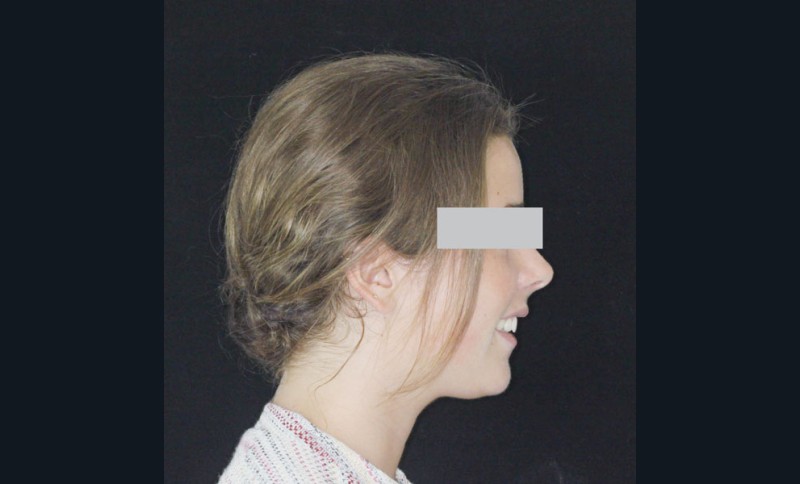

Le site des extractions s’est porté sur les secondes prémolaires. La justification de ces extractions passent par la résolution de l’encombrement sans effondrer le prémaxillaire.

La résolution de la classe II squelettique n’est aucunement recherchée au travers des extractions mais par une mécanique interarcade.